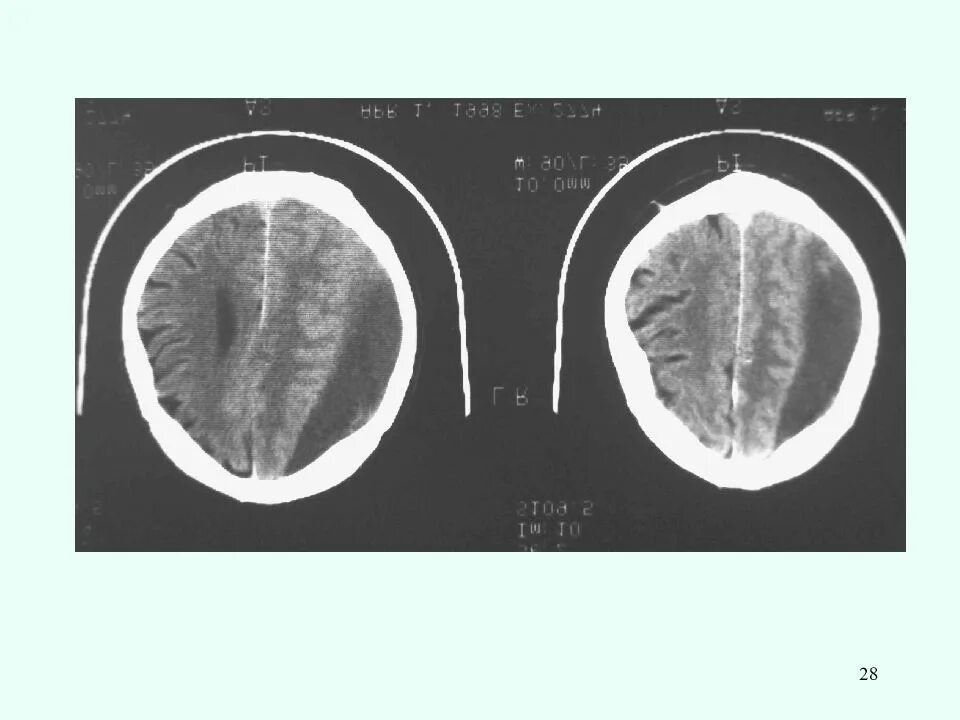

Закрытый черепно мозговой перелом